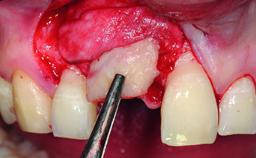

A 49-year-old female patient was referred for implant therapy to replace the upper right central incisor (tooth 11). The tooth had been assessed by an endodontist who diagnosed a vertical fracture of the root. The tooth had a hopeless prognosis and needed to be extracted. The patient was healthy and was not taking any medications. She was allergic to penicillin. The patient had high esthetic demands but her expectations were realistic. The extraoral examination revealed no facial asymmetries. The right temporomandibular joint demonstrated an opening click but was otherwise asymptomatic. The lip line was high with a significant gingival display.

Bone Augmentation Simultaneous|Vertical

Augmentation Materials Autogenous chips|Xenogenous|Membrane

Bone Volume Deficient vertically or deficient vertically AND horizontally

Anatomic Risk High

Esthetic Risk High

Complexity High